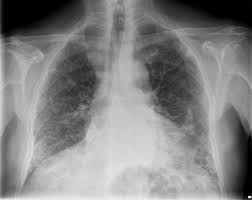

Asbestosis Radiology Reference Article Radiopaedia Org

Asbestosis Radiology Reference Article Radiopaedia Org from prod-images-static.radiopaedia.org

Gejala asbestosis mungkin tidak berkembang sehingga 20 tahun setelah terdedah, menunda rawatan.berpotensi. Asbestos terdiri dari serat silikat mineral dengan komposisi kimiawi yang berbeda. 3,5,9,23 pengobatan bersifat paliatif, beberapa obat yang digunakan diantaranya: Asbes sendiri merupakan serat silikat tahan panas yang banyak digunakan dalam berbagai industri, pelapis lantai, dan atap, terutama sebelum tahun 1970. Istilah asbestosis pertama kali dikemukakan oleh cooke pada 1927, setelah pada 1906 dilaporkan kasus kematian akibat asbestos. Pengertian asbestosis adalah pneumokoniosis yang disebabkan oleh akumulasi pajanan serat asbestos. Gejala, penyebab, diagnosis, dan pengobatan. Asbes adalah suatu jenis mineral yang biasa digunakan untuk pemasangan lantai atau atap bangunan.